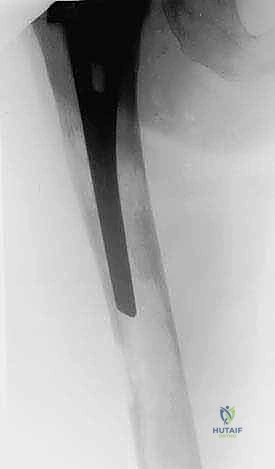

1. التثبيت الوقائي الداخلي (Prophylactic Internal Fixation)

إذا أظهرت الأشعة أن العظم ضعيف جداً وعلى وشك الانكسار، يقوم الدكتور هطيف بوضع أسياخ نخاعية معدنية (Intramedullary Nails) أو شرائح ومسامير متطورة داخل العظم لتدعيمه ومنع الكسر قبل حدوثه. هذه الجراحة الاستباقية توفر على المريض آلاماً مبرحة ومضاعفات خطيرة.

| جسم عظم الفخذ أو الساق | كسر مرضي كامل أثناء التحميل. | التثبيت بمسمار نخاعي تشابكي (Intramedullary Nailing). |